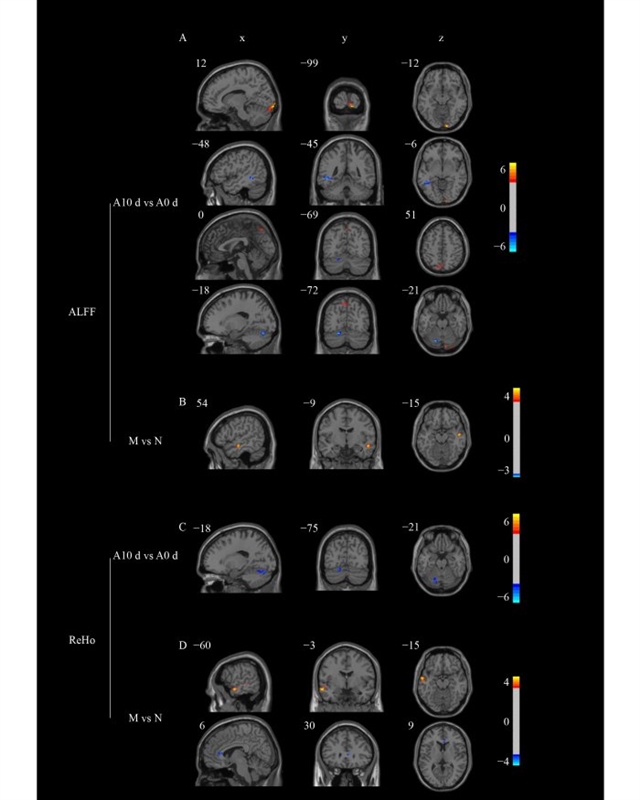

结果显示,针灸治疗显著降低了患者的视觉模拟量表评分(疼痛程度)、匹兹堡睡眠质量指数评分(睡眠质量)及偏头痛特异性生活质量问卷评分(生活质量影响),效果优于假针灸组;而空白对照组各项指标无显著变化,且所有治疗组均未出现局部血肿或头痛加重等不良反应。功能性磁共振成像分析发现,针灸治疗后患者舌回、默认模式网络(楔前叶等)及小脑等脑区的低频振幅(ALFF)和区域同质性(ReHo)值发生了显著改变,而假针灸组未观察到脑区活动的明显变化(图2)。

图2 各组间低频振幅(ALFF)与区域同质性(ReHo)的显著差异